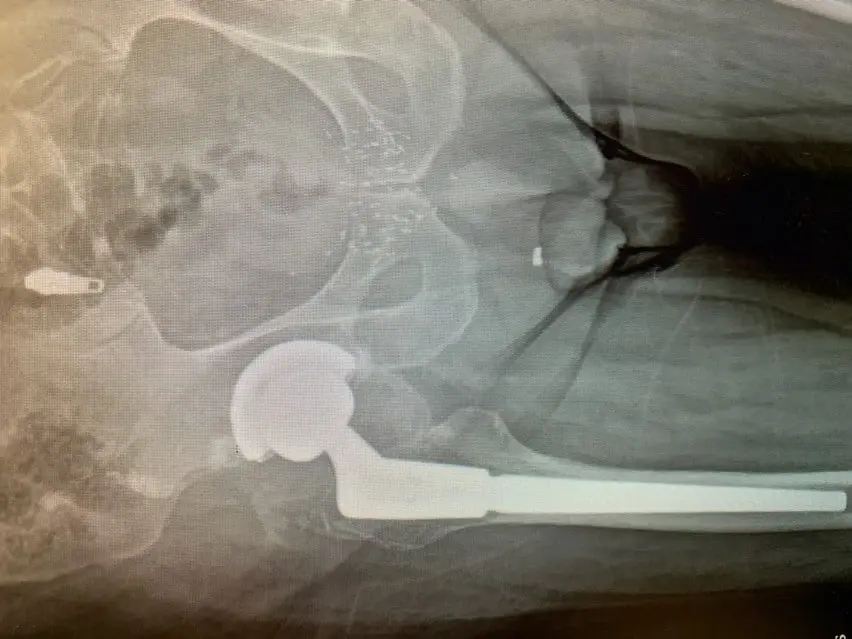

We carefully removed the femoral component and the plastic liner of the acetabular component – testing of the metal shell revealed it to be stable so it was decided this part of the original procedure would remain intact.

We prepared and inserted the revision femoral component without event and trialed femoral head components with trial acetabular liner components to ensure the hip remained stable. Once we were satisfied with our component sizes, definitive components were placed and the procedure was completed.